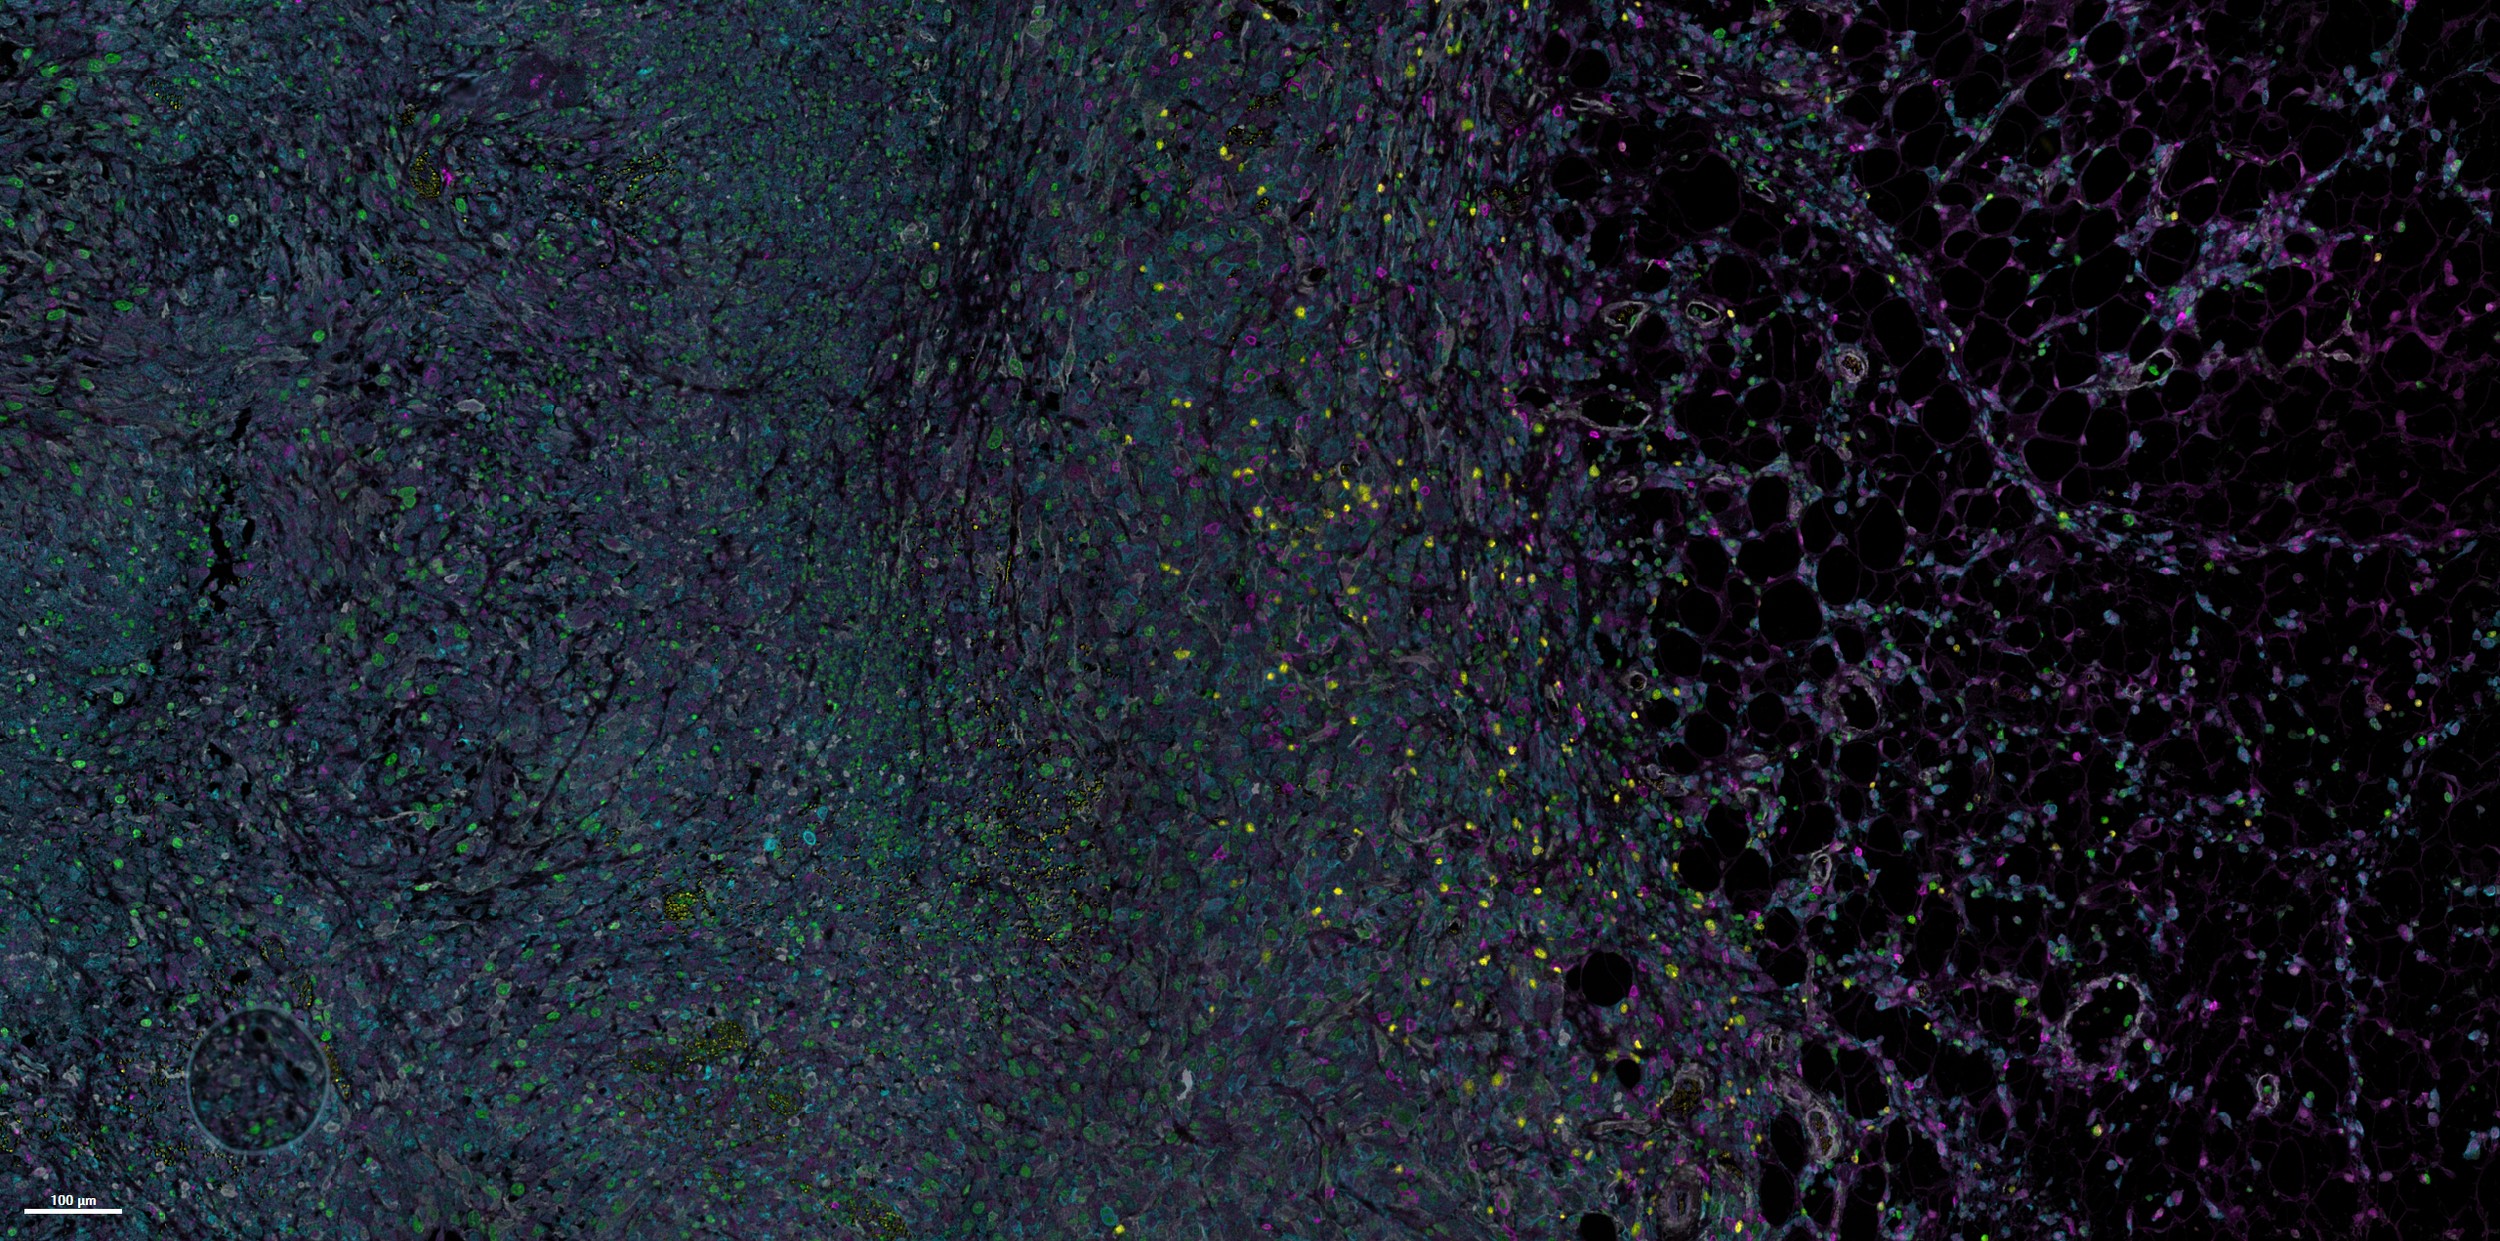

We develop immune-compatible drug and gene delivery systems to overcome biological barriers limiting the safety, durability, and effectiveness of advanced therapeutics

We develop immune-compatible drug and gene delivery systems to overcome biological barriers limiting the safety, durability, and effectiveness of advanced therapeutics